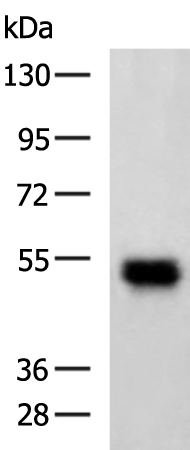

分类: 科研抗体货号: P00725别名: TAU; MSTD; PPND; DDPAC; MAPTL; MTBT1; MTBT2; tau-40; FTDP-17; PPP1R103应用: WB反应种属: Human, Mouse, Rat